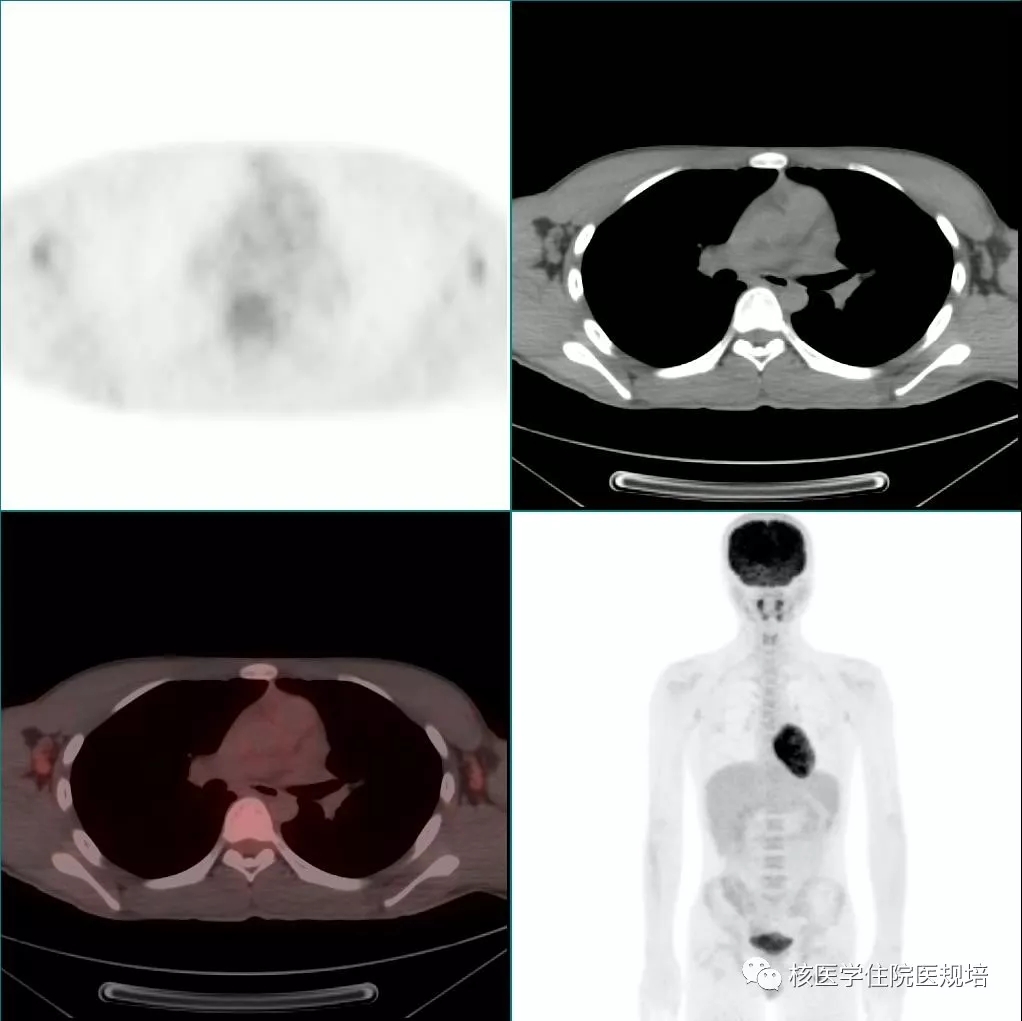

隔日再次行胸部 FDG PET/CT显像。显像前连续两餐进食低碳水化合物、高脂食物(第一餐为2只猪手,第二餐为5个茶叶蛋),第二餐4h后开始显像。与前次显像对照,除肿物显影外,左室其余心肌未见明显FDG摄取;前侧壁至心尖处占位表现为FDG摄取增高灶(SUVmax5.3),边界较清晰,范围约4.0×2.8×4.5cm,并侵犯乳头肌(图7)。

图7

本例患者在常规显像准备条件下左室占位区域FDG摄取情况受心肌生理性摄取影响观察欠满意,而饮食控制后再次显像,病变显示似有“水落石出”之感觉。通过这个病例想提示大家,在临床工作中遇到心脏及心包占位性病变或系统性疾病累及纵隔区域时(此种情况可见于自身免疫性疾病,如结节病、IgG4相关疾病、系统性淀粉样变、特发性炎性肌病等),应事先想到对患者进行特殊的检查前准备。